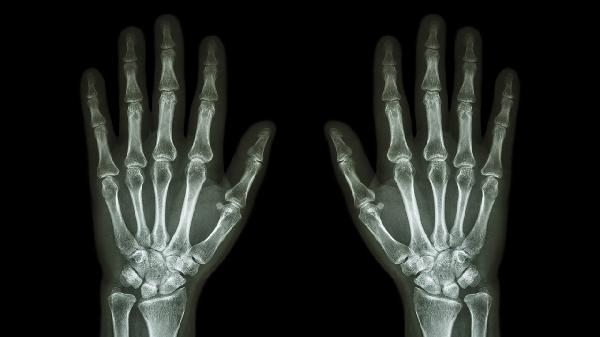

退行性骨关节炎多见于中老年人,关节软骨磨损后可能引发刺痛,晨起时僵硬感明显。X线检查可见关节间隙狭窄。可遵医嘱使用硫酸氨基葡萄糖胶囊、双醋瑞因胶囊等软骨保护剂,配合关节腔注射玻璃酸钠。